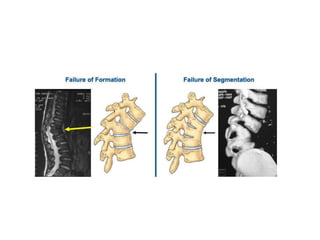

Congenital kyphosis

• It is the least common type of abnormal

kyphosis.

• It is caused by abnormal development of the

vertebrae prior to birth.

• Occurs due to fusion of many vertebrae

together.

Congenital kyphosis • Itis the least common type of abnormal kyphosis. • It is caused by abnormal development of the vertebrae prior to birth. • Occurs due to fusion of many vertebrae together.